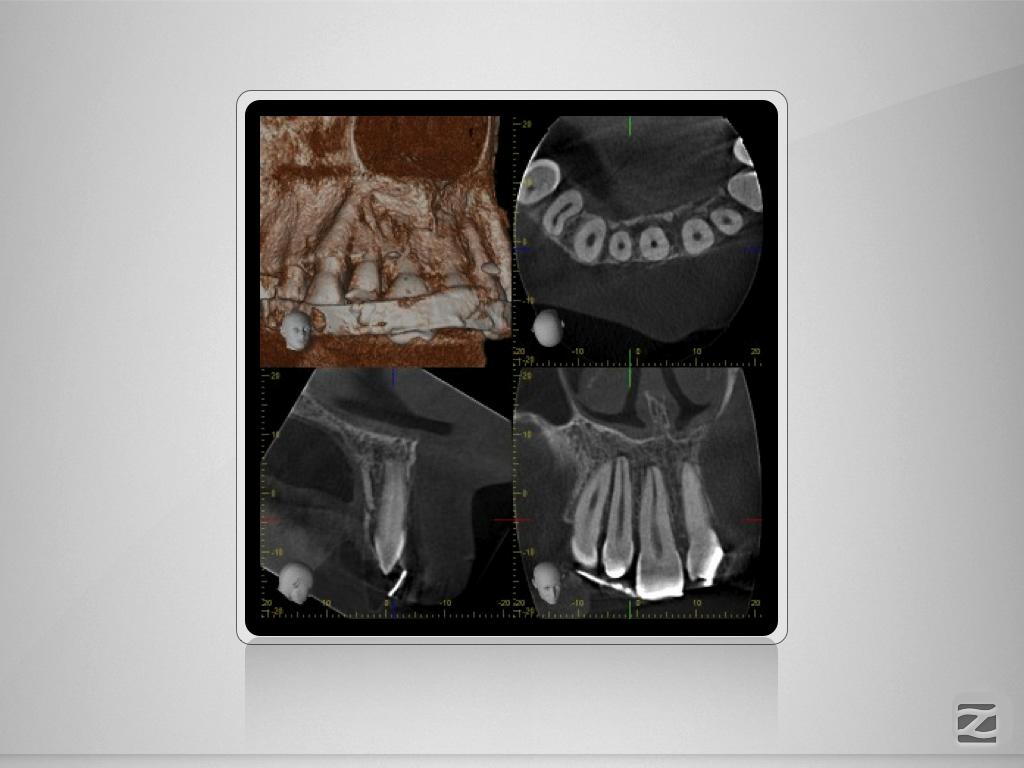

Multitrauma D.009

Mehrfach-Trauma